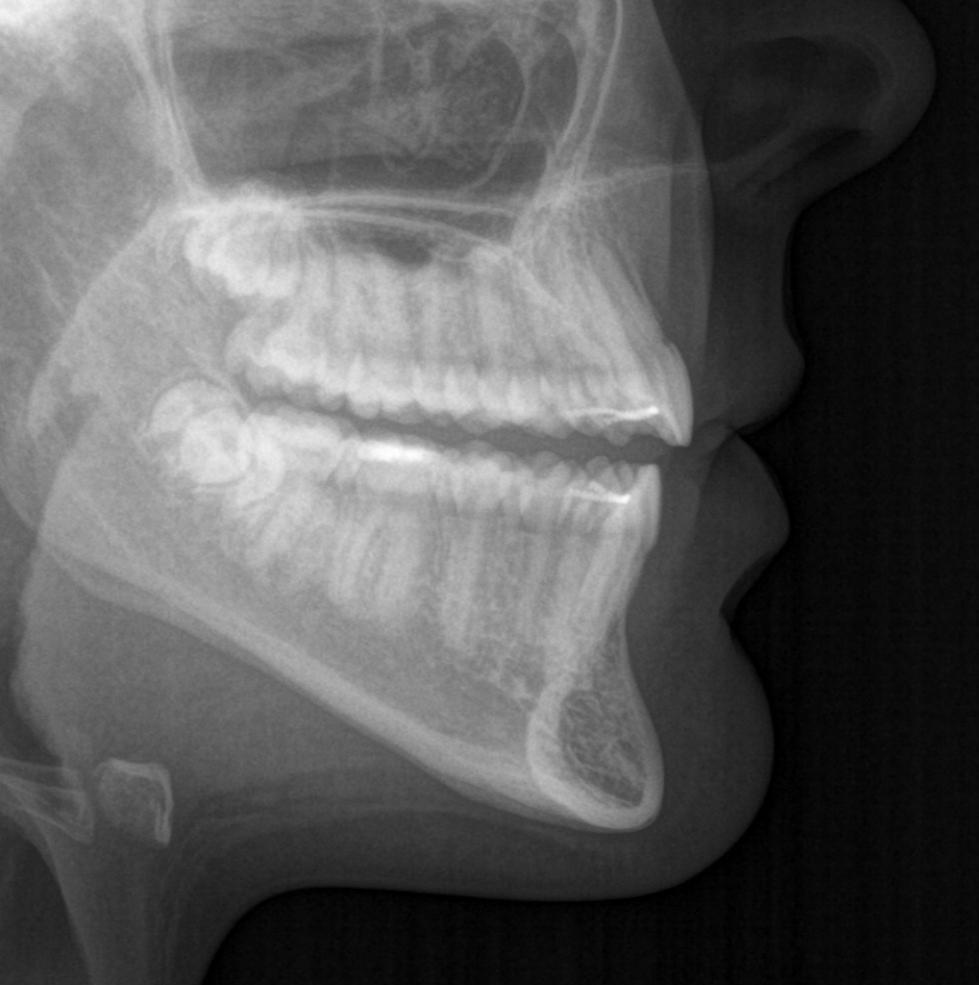

Głównym problemem był zgryz otwarty przedni, a także rotacje zębów oraz mała ekspozycja siekaczy w uśmiechu.